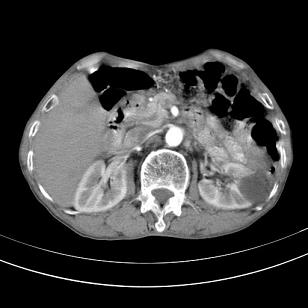

标题: 男,65岁,反复右上腹痛, [打印本页]

标题: 男,65岁,反复右上腹痛,

胃镜提示十二指肠占位